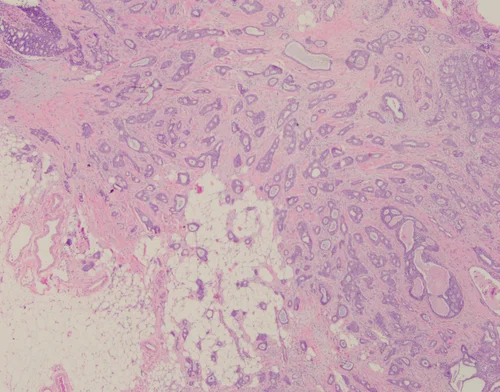

Invasive Ductal Carcinoma, Grade 3, With Extensive Lymphovascular Invasion

Invasive ductal carcinomas are the most common type of invasive breast cancer (70-75% of cases). They are heterogeneous with regards to pathologic features and clinical course.

Histologically, IDCs vary with regard to growth pattern (eg tubular vs solid), cytologic features, mitotic activity, stromal desmoplasia, and extent of associated in-situ component. The degree of gland formation, nuclear atypia, and mitotic activity are considered together in determining the combined histologic grade.

Three universally accepted biomarkers are used in daily practice currently: estrogen receptor (ER), progesterone receptor (PR), and HER2. Studies have shown about 70-80% of IDCs are ER+ and 15% show HER3 overexpression.